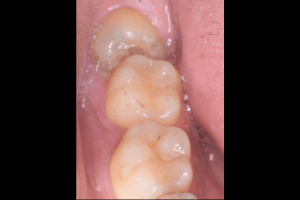

右上下の親知らず抜歯症例

- 右上抜歯前の写真

- 右上抜歯後の写真

- 右下抜歯前の写真

- 右下抜歯後の写真

| 抜歯内容 | 右上8番普通抜歯 右下8番の半埋伏抜歯 |

| 治療方針 | 右上8番と上顎洞との位置関係と、右下8番と神経の位置関係を確認するためにCT撮影を行いました。 右下8番は半埋伏なので歯ぐきを切開後、骨を切削したり、歯を分割して抜歯しています。 切開した歯ぐきの箇所は2箇所縫合し、後日抜糸しています。 右上8番は切開することなく抜歯しました。 |